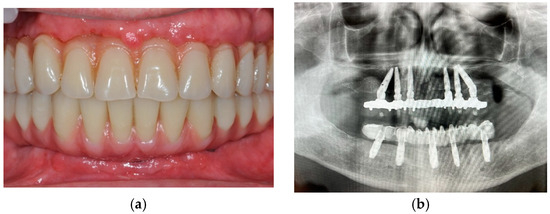

3. Case Presentation